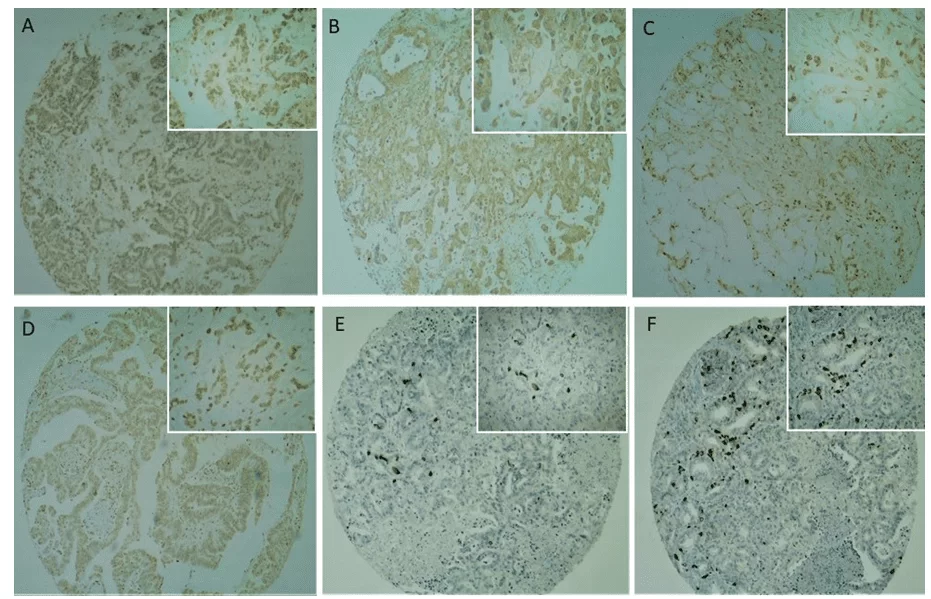

Cd133 Immunostainierung war in der Plasmamembran und Zytoplasma mit mäßiger bis starker Intensität vorhanden (Abbildungen 2C und 2D), mit einer überwiegend starken Intensität. Eine positive oder negative Reaktion wurde mit der in der Studie verwendeten Positivkontrolle (Plazenta) bestätigt. Keine CD133-Immunreaktivität wurde bei normalem pankreatischem duktalen Epithel beobachtet (Abbildung 2).

Abb. 2. Immunhistochemische Analyse von Krebsstammzellenmarkern in TMA-Pankreaskrebsproben. (2A, 2B) Die CD24-Expression wurde hauptsächlich im Zytoplasma von Tumorzellen beobachtet. (2C, 2D) Die CD133-Expression wurde hauptsächlich in der Membran und im Zytoplasma von Tumorzellen beobachtet, die selten nuklear sind. (2E, 2F) Die OCT4-Expression wurde im Nukleo von Tumorzellen mit einer fokalen Expression und starker Intensität beobachtet. Niedrigstes Vergrößerungsfeld (40x) werden im globalen Panel und das höchste Vergrößerungsfeld (100x) im reduzierten Bedienfeld dargestellt.

CD24-Immunostainierung (Abbildungen 2A und 2B) war in der Plasmamembran und im Zytoplasma sowohl schwach als auch mäßig (41,6%) und stark (58,3%) intensitätsweise, aber mit einer schwächeren Intensität im Vergleich zu CD133 (Abbildungen 2C und 2D). Die positiven und negativen Reaktionen wurden mit der in der Studie verwendeten positiven Kontrolle (Plazenta) bestätigt. Tabelle 4 zeigt die beschreibende Analyse der Variablen zusammen mit der Überprüfung ihrer Assoziation mit CD24 Positivität, die durch Fishers genauen Test gegeben wird. Ein positives CD24-Signal wurde bei 98,3% der Männer beobachtet, aber es gab keinen Zusammenhang zwischen Geschlecht und CD24-Positivität (P = 0,343). Nur die Art der entnommenen Probe und die palliative Behandlung waren signifikant mit dem CD24-Signal assoziiert, bei einem Signifikanzniveau von 5% (P = 0,010 bzw. 0,042).

OCT4 IMMUNOSTAINING IN CANCER STEM CELLS IN PANCREATIC DUCTAL ADENOCARCINOMA CELLS

Die OCT4-Immunfärbung zeigte ein anderes Muster im Vergleich zu den anderen getesteten Antikörpern. Die Häufigkeit positiver Fälle war nicht so hoch wie bei den beiden anderen getesteten Antikörpern, aber wenn positiv, war ihre Intensität sehr stark (Abbildungen 1E und 1F). Immunostaining trat in 31,5% der Fälle im Tumorzellkern auf und färbte 68,7% der analysierten Tumoren nicht. Keine OCT4-Immunreaktivität wurde im normalen pankreatischen duktalen Epithel beobachtet. Keine Variable wurde signifikant mit OCT4-Signal assoziiert, bei 5% Signifikanzniveau. Das Durchschnittsalter der OCT4-positiven Gruppe betrug 62,62 Jahre und 63,23 Jahre in der OCT4-negativen Gruppe. Es gab jedoch keinen signifikanten Unterschied zwischen den Altersgruppen in Bezug auf das Alter (P = 0,547).